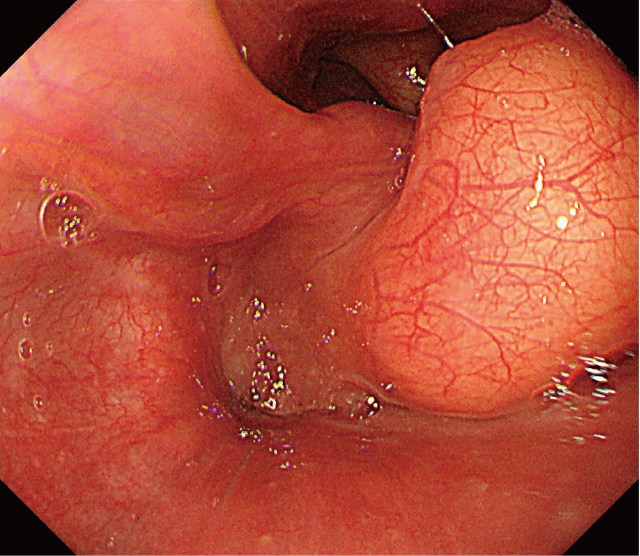

上部内視鏡検査:下咽頭右梨状陥凹に,表面平滑で黄色調の粘膜下腫瘍を認める(Figure 1).腫瘍は披裂喉頭蓋ひだに付着し,右側壁に連続しているように観察された(Figure 2).

腫瘍は披裂喉頭蓋ひだに付着し,右側壁に連続している.